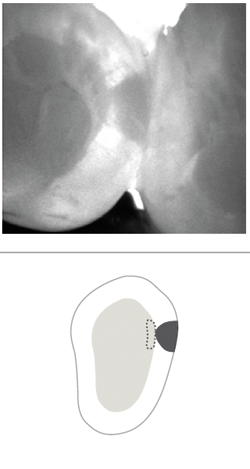

A recent example shows how a CariVu image can provide peace of mind to even the most doubting people. A patient arrived at my office with the problem of sensitivity on chewing. He told me that he did not think that the tooth was cracked. As a science education teacher at a local college, he felt confident in his self-diagnosis, and narrowed his problem down to one of two teeth. CariVu images showed him that in actuality, both teeth had cracks. The first CariVu image shows a crack on the mesial of tooth #3 (Fig. 4), and the second image shows cracks on the distal of tooth #3 and on the mesial of tooth #2 (Fig. 5). Of note is the dark area around the crack on #2 that represents the spreading caries that originate from the fracture. When faced with the evidence on the CariVu images, this skeptical science person now understood where his sensitivity was originating from, and he was eager to make the appointment for the appropriate repairs to those teeth.